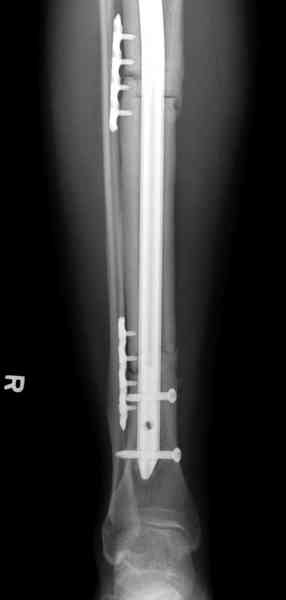

conference мы разбирали похожий случай, ложный сустав большеберцовой кости после резекции опухоли.

К нашему онкологу-ортопеду обратился больной с жалобами на боли в голени, из рассказа - год назад была сделана биопсия большеберцовой кости, но название заболевания "не запомнил”.

Оперирован в военном госпитале с заменой сегмента

аллокостью большеберцовой кости и после демобилизации явился для постоянного наблюдения по месту жительства.

Наши имели проблему со сращением, пришлось им сделать динамизацию, дополнительную аутопластику.

Снимки представлены.